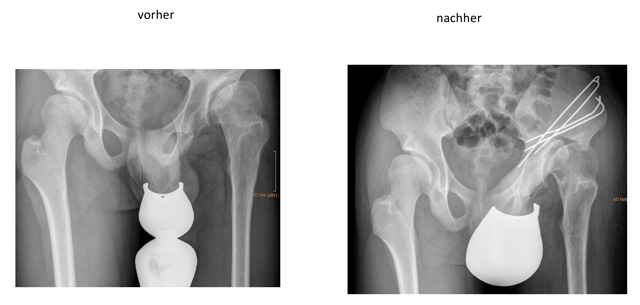

Bei der Operation wird der Beckenknochen in der Umgebung der Pfanne kontrolliert durchtrennt und die Pfanne dann neu orientiert und meist mit Schrauben wieder fixiert. Dadurch kann die Pfanne bezüglich Tiefe und Ausrichtung verändert werden.

- Triple-Osteodomie